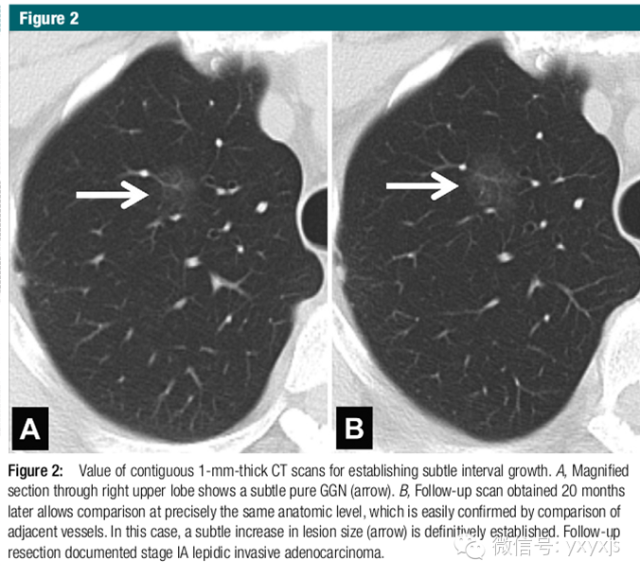

2 孤立的、直径大于5mm的纯GGO,3月后复查,以观察病变是否消失。如持续存在,则每年复查,至少持续3年。

病理上为AAH、原位腺癌和一少部分微浸润腺癌。不建议使用抗生素。PET检查价值不大。CT引导穿刺不推荐,阳性率较低。

如果病变增大或病变密度增高,可采取手术治疗,术式推荐胸腔镜楔形手术、肺段或亚段切除。